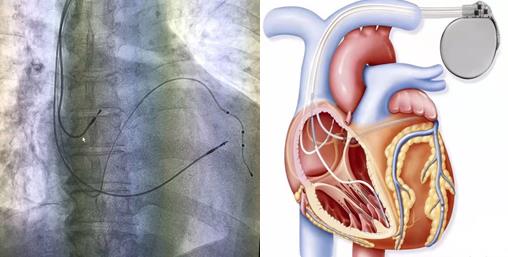

手術(shù)過(guò)程:手術(shù)開(kāi)始,患者在局部麻醉下,順利穿刺左側(cè)腋靜脈成功后,依次植入右室主動(dòng)電極、過(guò)鞘管送遞長(zhǎng)鞘、沿長(zhǎng)鞘送十極至冠狀動(dòng)脈竇口,推送進(jìn)冠狀竇遠(yuǎn)端,沿十極電極遞送長(zhǎng)鞘至冠狀竇,取出十極電極,在雙導(dǎo)絲支撐下送造影球囊進(jìn)行造影,選擇合適的心左側(cè)靜脈后,順利植入左室電極,再植入右房主動(dòng)電極,多體位投照各電極位置合適、測(cè)試起搏參數(shù)均符合要求,遂固定電極后植入起搏器。歷經(jīng)2.5小時(shí), 三腔起搏器植入術(shù)順利完成,患者各項(xiàng)參數(shù)檢測(cè)均正常。

目前常用的“單(雙)腔心臟起搏器”均只能治療心動(dòng)過(guò)緩,但三腔起搏器可實(shí)現(xiàn)心臟再同步化治療(CRT)目的,不但具有治療心動(dòng)過(guò)緩的功能,還能解決由于患者左右心室收縮不同步而導(dǎo)致的心衰癥狀。它是在傳統(tǒng)的雙腔起搏(右心房,右心室起博)的基礎(chǔ)上增加了左心室起搏,左室起搏電極經(jīng)右房的冠狀靜脈竇開(kāi)口,進(jìn)入冠狀靜脈左室后側(cè)壁支起搏左室,通過(guò)多部位起搏恢復(fù)左右心室同步收縮,增加左心室充盈時(shí)間,減少室間隔矛盾運(yùn)動(dòng),減少二尖瓣返流,從而改善患者的心臟功能,甚至可以讓擴(kuò)大的心臟回縮,提高運(yùn)動(dòng)耐量以及生活質(zhì)量。